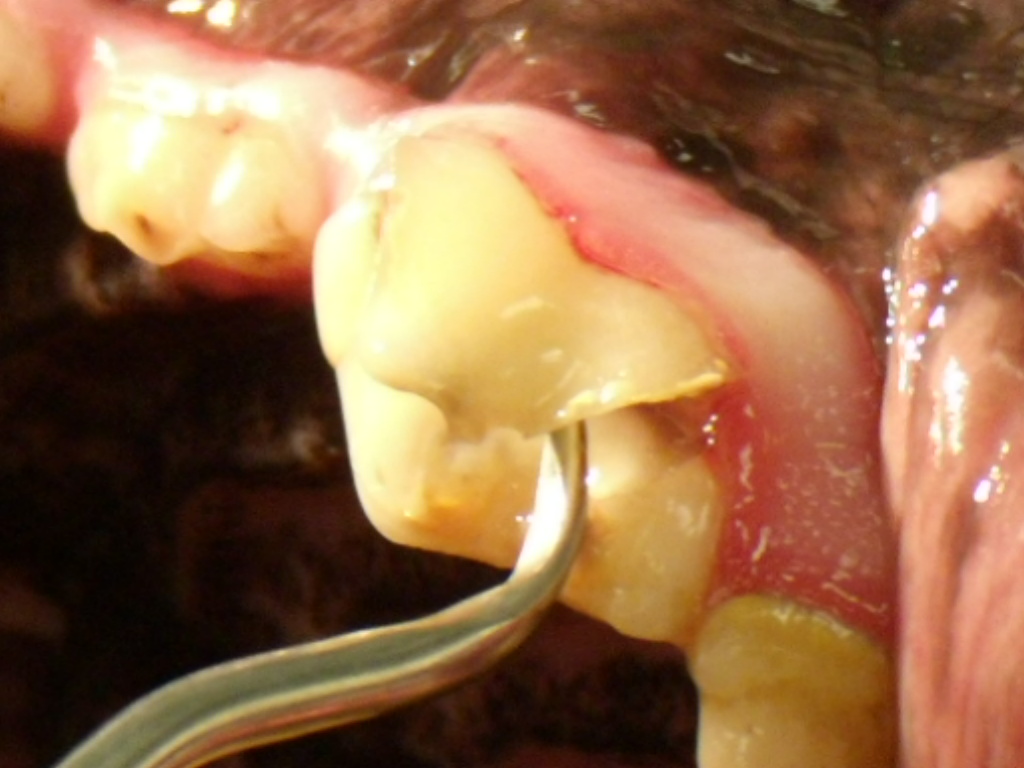

A slab fracture happens when a dog bites down on something hard at just the right angle and with just the right amount of force that it breaks a flake or slab off of the tooth. It could break off a large or small piece.

Broken teeth can lead to a bacterial infection that destroys the root of the tooth and results in bone loss, requiring extraction or root canal therapy. We started antibiotic therapy, put abby on pain medication and referred her to a nearby veterinary dentist for definitive a word to the wise is sufficient. Dental fractures can also occur when our pets are victims of trauma, such as being hit by a car. My three year old sheltie mix broke her fourth upper tooth. If you would like to learn more about how this condition affects cats, please visit this page in the petmd. A slab fracture develops on the carnassial tooth (or any other tooth for that matter) when the dog bites down on a hard object at just the right angle and with just the right force to break off a flake or slab of tooth. The problem was an infected tooth root stemming from a slab fracture. Dale kressin dvm, favd, davdc and animal dentistry and oral surgery specialists, llc oshkosh. As a result, decreased appetite or interest in eating can occur. Fractured teeth are common and typically occur when our pets chew on hard objects, like rocks, bones or antlers. You think you see a broken dog tooth. All information is peer reviewed. After dash's diagnostic procedure, dr. Banker and i met to discuss his findings. A slab fracture happens when a dog bites down on something hard at just the right angle and with just the right amount of force that it breaks a flake or slab off of the tooth. He may drop his food while chewing, not pick the food up properly, or chew. Items like bones, antlers, and very hard plastic can actually cause teeth to break.